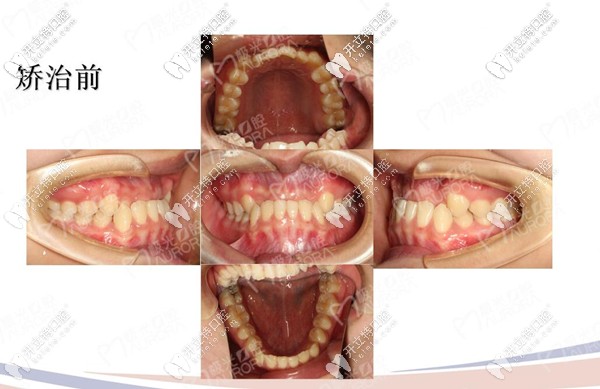

戴牙套之前的樣子

醫(yī)助結合我的需求給我介紹的醫(yī)生也很有耐心,拍片檢查后看我雖然是地包天,但是我的牙周情況良好屬于牙性因素的反合。

牙片真是個好東西,我終于全面看到了自己牙齒,說實話,有點嫌棄啊,醫(yī)生給我介紹的隱形矯正和鋼絲矯正,但是為了美觀和方便,我選擇的是隱適美隱形牙套,因為隱適美會對推磨牙后移的矯正速度減少,具體醫(yī)生咋說的,我給忘啦!嗚嗚!

地包天矯正前后對比圖